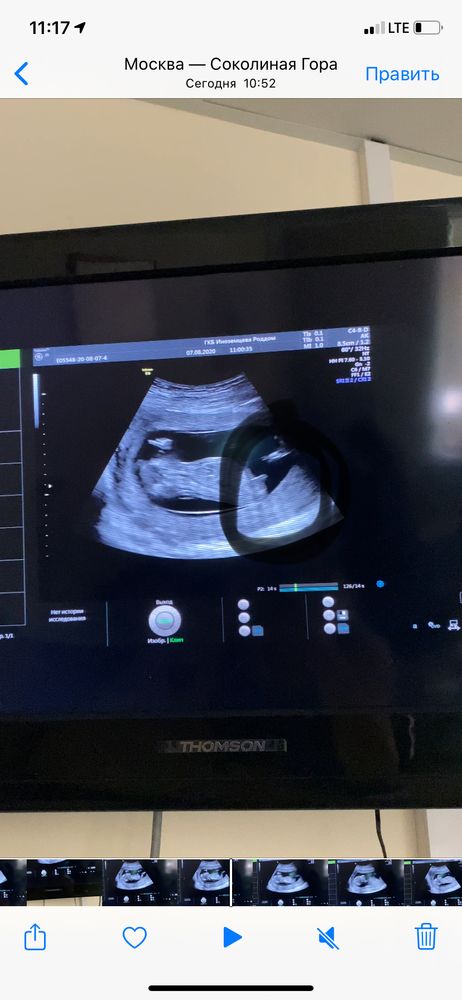

Вот и прошли первый скриннинг!!

УЗИ, КТГ, доплерВсем привет!наконец то и мы прошли первый скриннинг!врач сказал что по узи всё хорошо,кровь через 3 дня,но на руки мне ничего не дали😫никаких замеров,сказали всё передадут гинекологу,который ведёт беременность!

Как то быстро всё посмотрели,мин 10 всего!ещё спросили где прописана(наблюдаюсь я в Москве в жк,а прописанна в МО) сказали,что от этого зависят какие исследования нужно делать!вот этого я немного не поняла 😲

Пол сказать отказались,но разрешили заснять видео,ну я заскринила,мне кажется пипирка🤣

Если это половой бугорок все таки, то больше на девочку похоже )

Пипирки на таком сроке ещё быть не может, она отрастает только к 15-16 неделе 😉